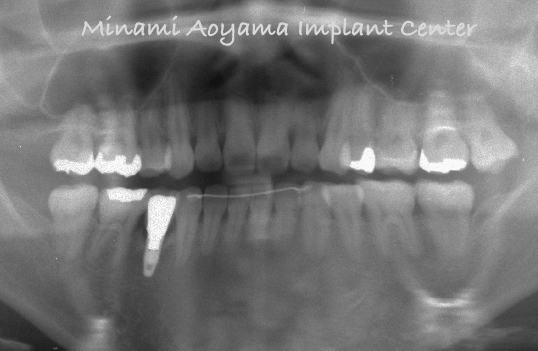

術前・術後のレントゲン写真です。寸分の誤差もなく予定どおり理想的な位置にインプラントが適切に埋入されております。

術前のレントゲン写真です。中切歯にはかなり太い金属の土台が入っており、これも歯根破折の原因でしたので、右側中切歯は抜歯しましたが、左側中切歯は土台のやりかえも行い、審美性、機能性ともに最大限の配慮を行いました。